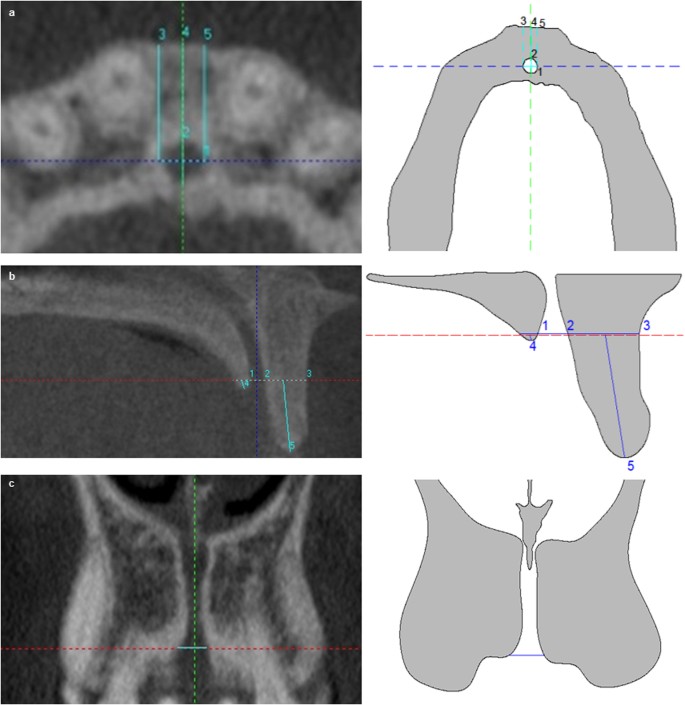

The measurements were carried out at 3 different levels above the NC, the buccal bone plate (BBP) and palatal bone plate (PBP). Measurements are simultaneously taken for all three anatomical planes (axial, sagittal and coronal) as follows.

Level 1

It is located based on the axial slice when the incisive foramen of NC is completely closed. In axial slice the following measurements were taken: (1) buccal-palatal diameter (bpD1) and transversal diameter (tD1) of NC. The bpD1 corresponded to maximum diameter between buccal and palatal bone cortical of NC; the tD1 is the maximum diameter perpendicular to bpD1; and, (2) BBP widths. The distance from BBP to buccal wall of NC at three points of NC: left (LW1), central (CW1) and right (RW1) (Fig. 1).

In coronal slice the following measurement was taken on the horizontal line: (1) NC diameter at level 1 (CD1) (Fig. 1).

In sagittal slice the following measurements are taken on the horizontal line: (1) BBP width at level 1 (BW1), (2) NC sagittal diameter at level 1(SD1) and (3) PBP width at level 1 (PW1). In addition, the following measurements are taken from the horizontal line to the inferior edges of BBP and PBP: (1) BBP length at level 1(BL1) and (2) PBP length at level 1 (PL1) (Fig. 1).

Level 2

It is located by moving the horizontal line to the middle point of NC length (NCL) on the sagittal plane. NCL is defined as the distance from the incisive foramina to foramina of Stenson.

In axial slice the following measurements were taken: (1) buccal-palatal diameter (bpD2) and transversal diameter (tD2) of NC. The bpD2 corresponded to maximum diameter between buccal and palatal bone cortical of NC; the tD2 is the maximum diameter perpendicular to bpD2; and, (2) BBP widths. The distance from BBP to buccal wall of NC at three points of NC: left (LW2), central (CW2) and right (RW2) (Fig. 2).

In coronal the following measurement was taken on the horizontal line: (1) NC diameter at level 2 (CD2) (Fig. 2).

In sagittal slice the following measurements were taken on the horizontal line: (1) BBP width at level 2 (BW2), (2) NC sagittal diameter at level 2(SD2) and (3) PBP width at level 2 (PW2). In addition, the following measurements were taken from the horizontal line to the inferior edges of BBP and PBP: (1) BBP length at level 2 (BL2) and (2) PBP length at level 2 (PL2) (Fig. 2).